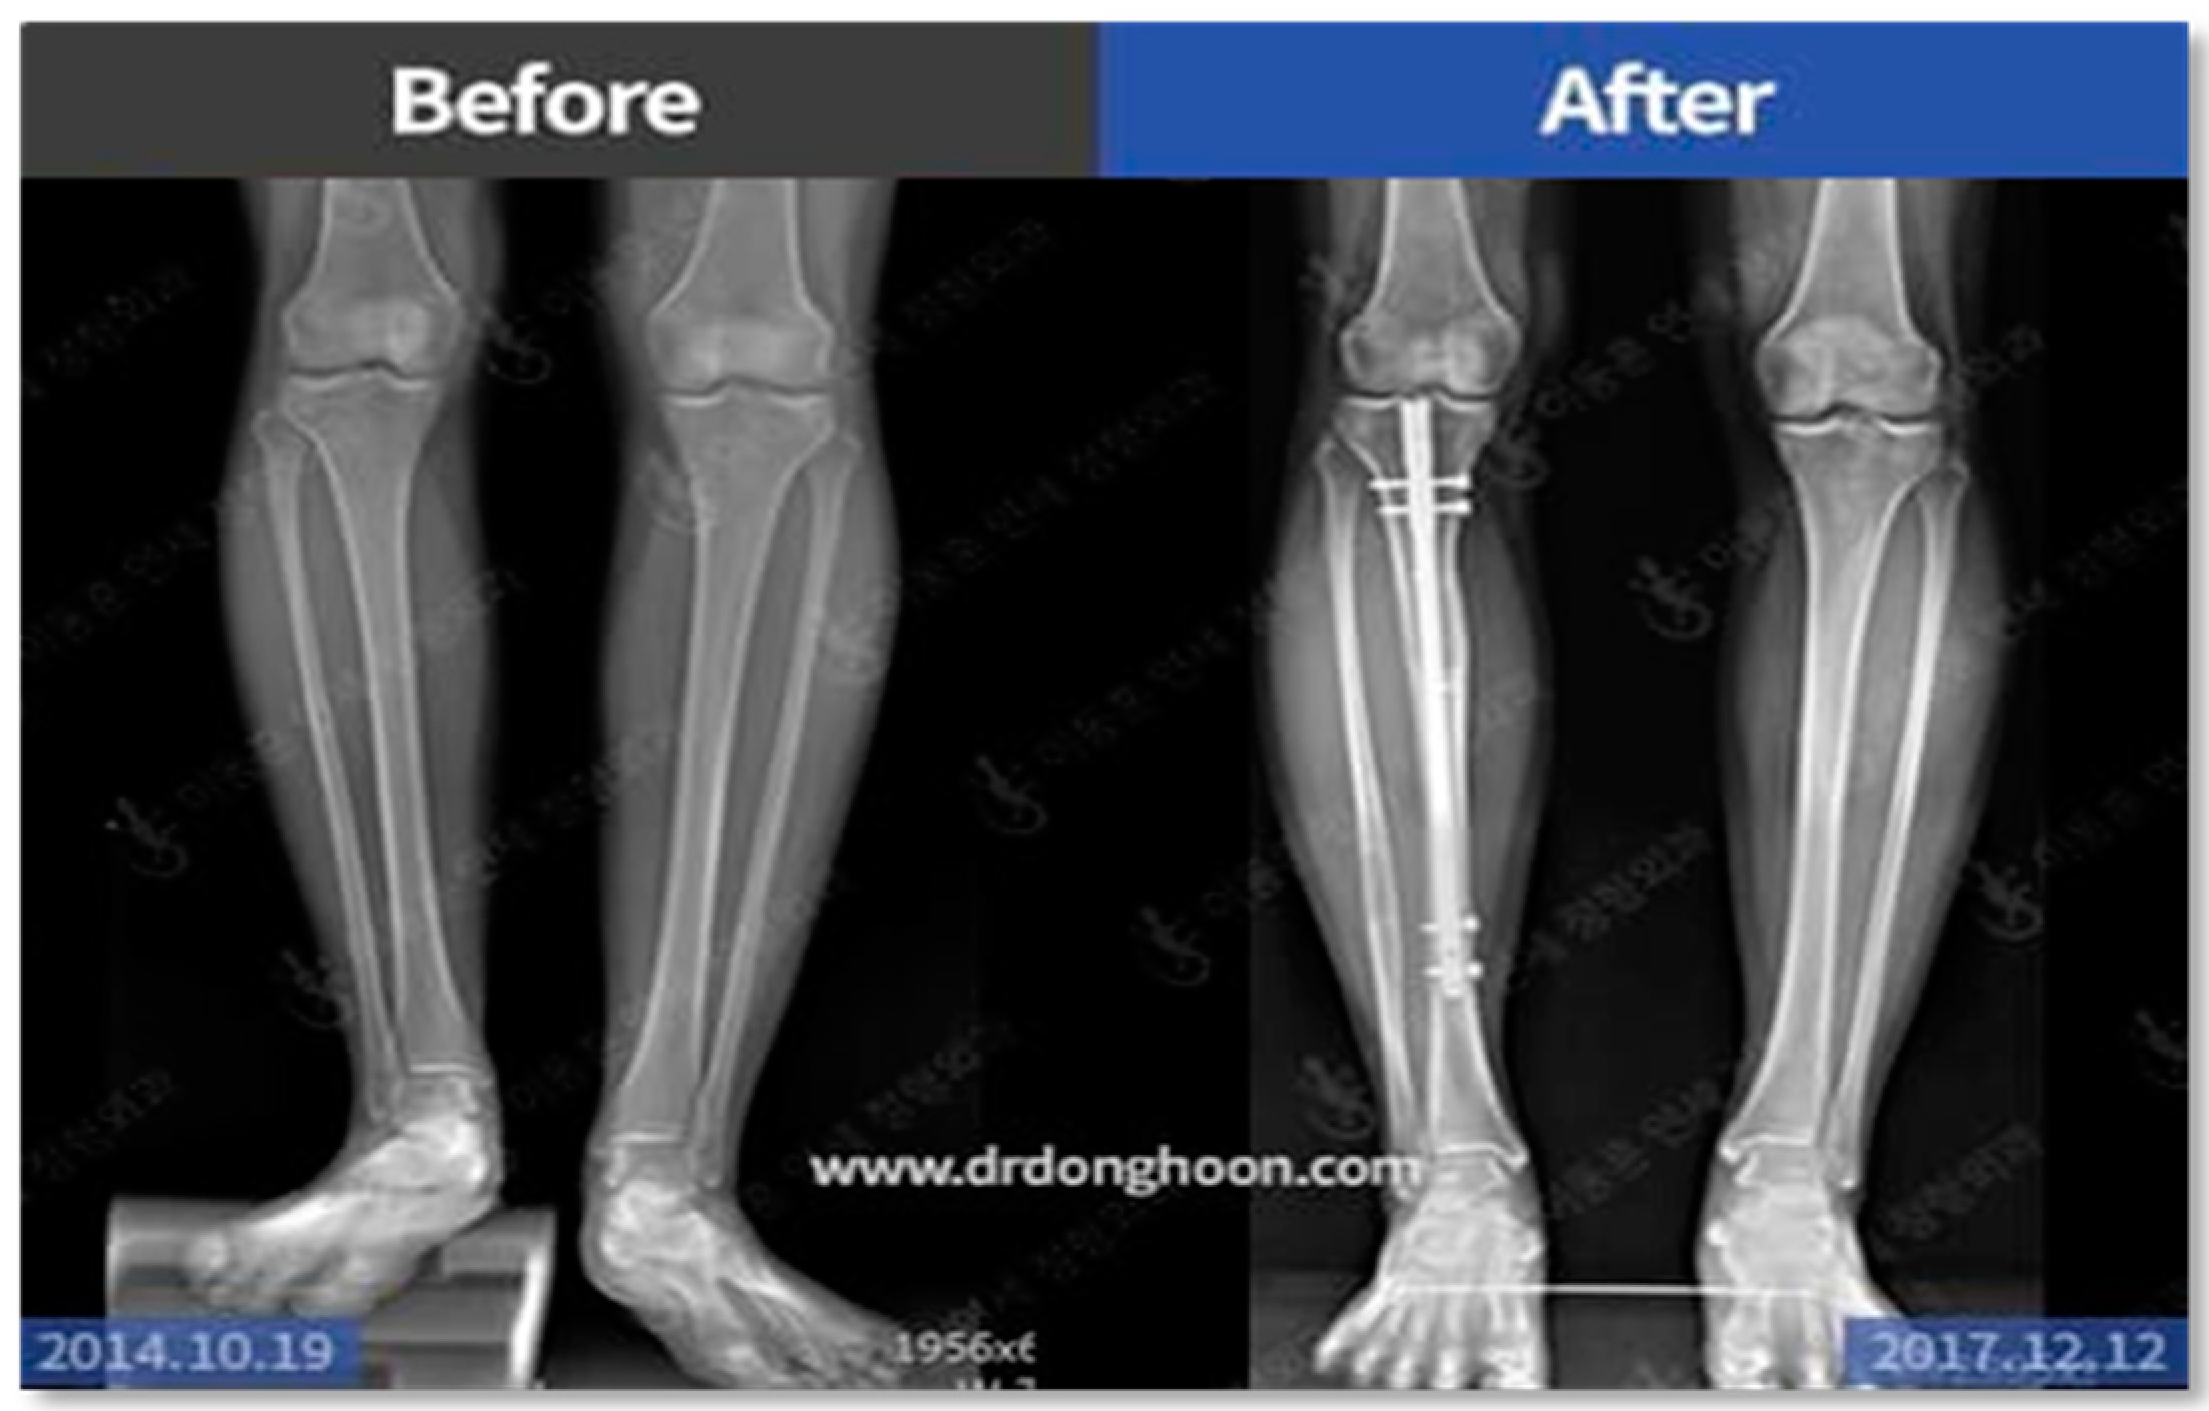

- Pre-Surgery Assessment: Before surgery, a thorough assessment of the patient’s leg is conducted. This involves analyzing the geometry and alignment of the leg, along with X-ray imaging, to determine suitability for limb lengthening. Factors like body weight are also considered to decide the appropriate osteotomy height [23,24,25,26,27].

- Osteotomy Procedure: This is the actual surgical phase where the femur bone is carefully cut into two parts to accommodate the implant. The implant is then securely fixed using screws, ensuring stability and precision in the lengthening process.